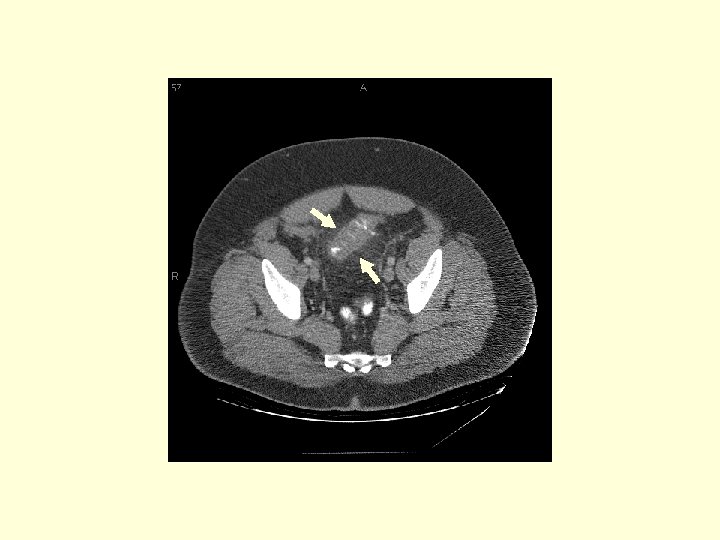

This is a patient with diverticulitis. Trace the sigmoid colon (white arrows) over the next 6 images and noted the wall thickening and the mesenteric fat stranding (circle).